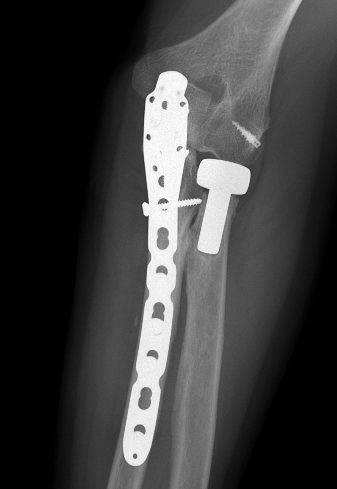

Olecranon plate + ORIF Type II coronoid process + radial head replacement

Olecranon plate with radial head replacement

Olecranon plate with radial head replacement + LCL repair

Olecranon plate + medial coronoid buttress plate + radial head replacement